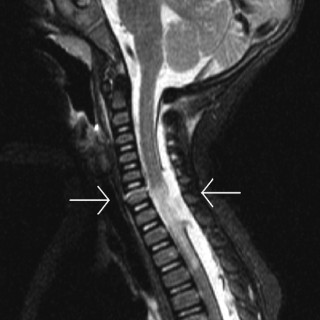

Ved Barneklinikken ved Oslo universitetssykehus, Ullevål, ble det lagt inn en 15 måneder gammel jente med feberperioder, blekhet, forstørret lever og milt. Blodprøver viste anemi, leukopeni, trombocytopeni, høyt ferritinnivå og høyt CRP-nivå. Pasienten viste seg å ha den sjeldne tilstanden hemofagocytisk lymfohistiocytose (HLH), som var utløst av en i Norge meget sjelden infeksjonssykdom, nemlig visceral leishmaniasis. Forfatterne presenterer en problemorientert utrednings- og behandlingsprosess. For en barnelege er dette meget interessant å følge, trolig også for leger innen andre deler av...